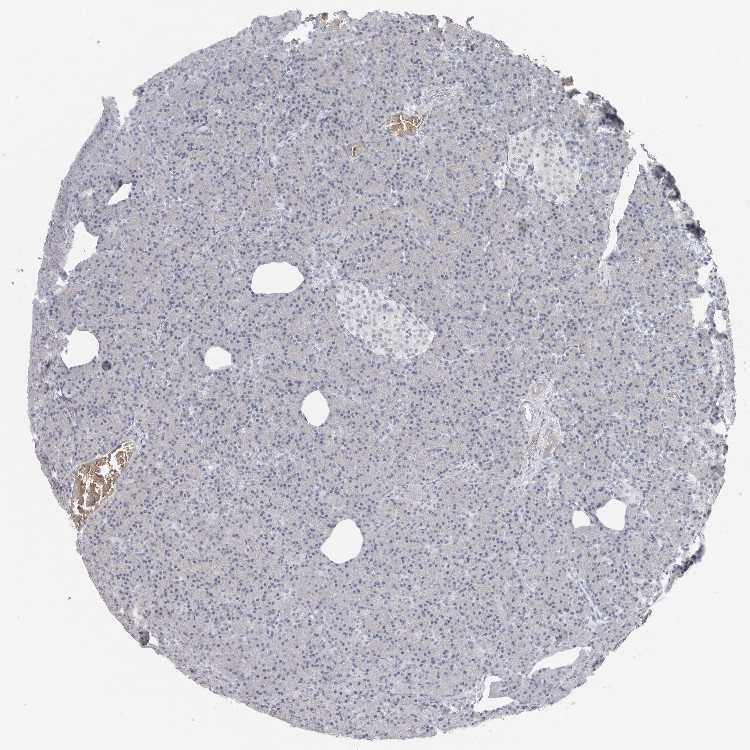

PANCREAS - Antibody stainingi

Antibody staining in the annotated cell types in the current human tissue is reported as not detected, low, medium, or high, based on conventional immunohistochemistry profiling in selected tissues. This score is based on the combination of the staining intensity and fraction of stained cells.

Each image is clickable and will lead to virtual microscopy that enables deeper exploration of all samples and also displays staining intensity scores, fraction scores and subcellular localization as well as patient and tissue information for each sample.

Antibody HPA028414

Exocrine glandular cells Not detected

Pancreatic endocrine cells Not detected